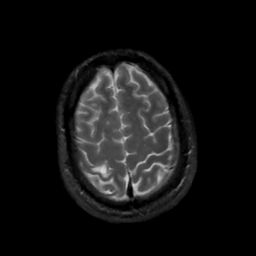

MR Study #5, March 10, 1991 -- Slice #43

[Home][Help][Clinical][Tour 1][Tour 2] Slice 43